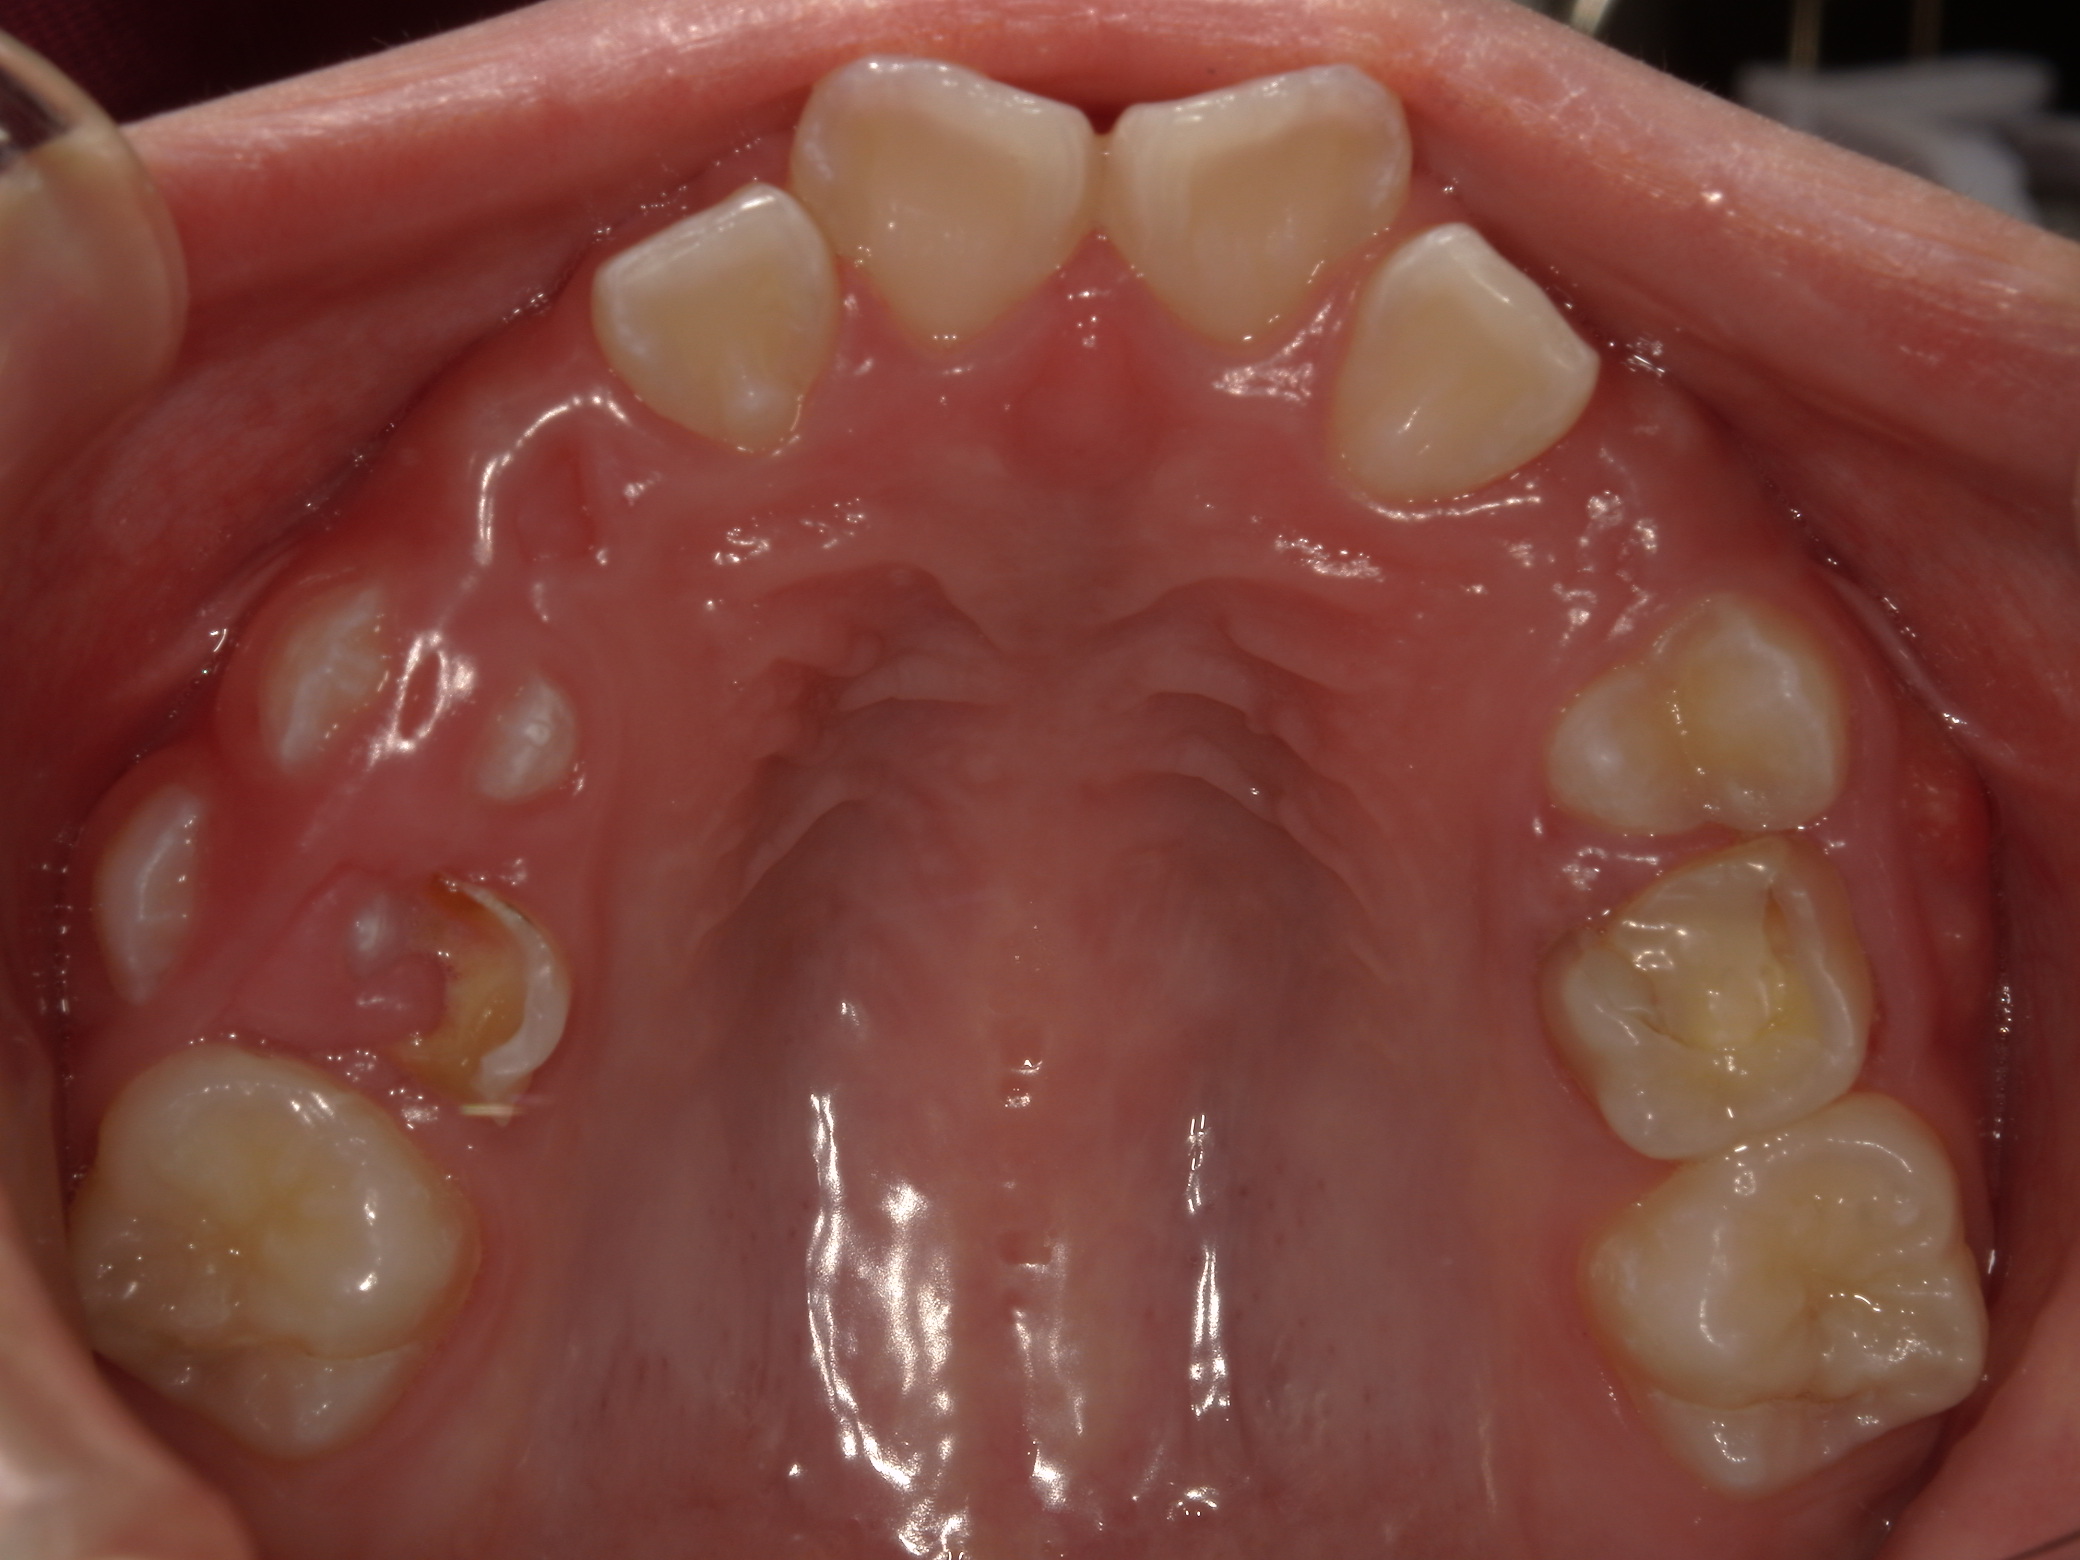

早期矯正治療 叢生症例①

主訴 | 歯の生えるスペース不足が懸念され、歯列の乱れ(叢生)を整えるために来院された患者様です。 |

---|---|

診断結果 | 7歳1か月の男児。 叢生の進行が見込まれると診断されました。 |

治療内容 |

|

治療後の経過 | 1年3か月の動的治療を通じて、上下顎の歯列が改善されました。 治療終了後は3〜4か月に一度の定期検診を継続しており、本格矯正治療の開始時期を判断していく方針です。 |

治療期間 | 動的治療期間:1年3か月 通院回数:11回 |

治療費用 | 420,000円(税別) |